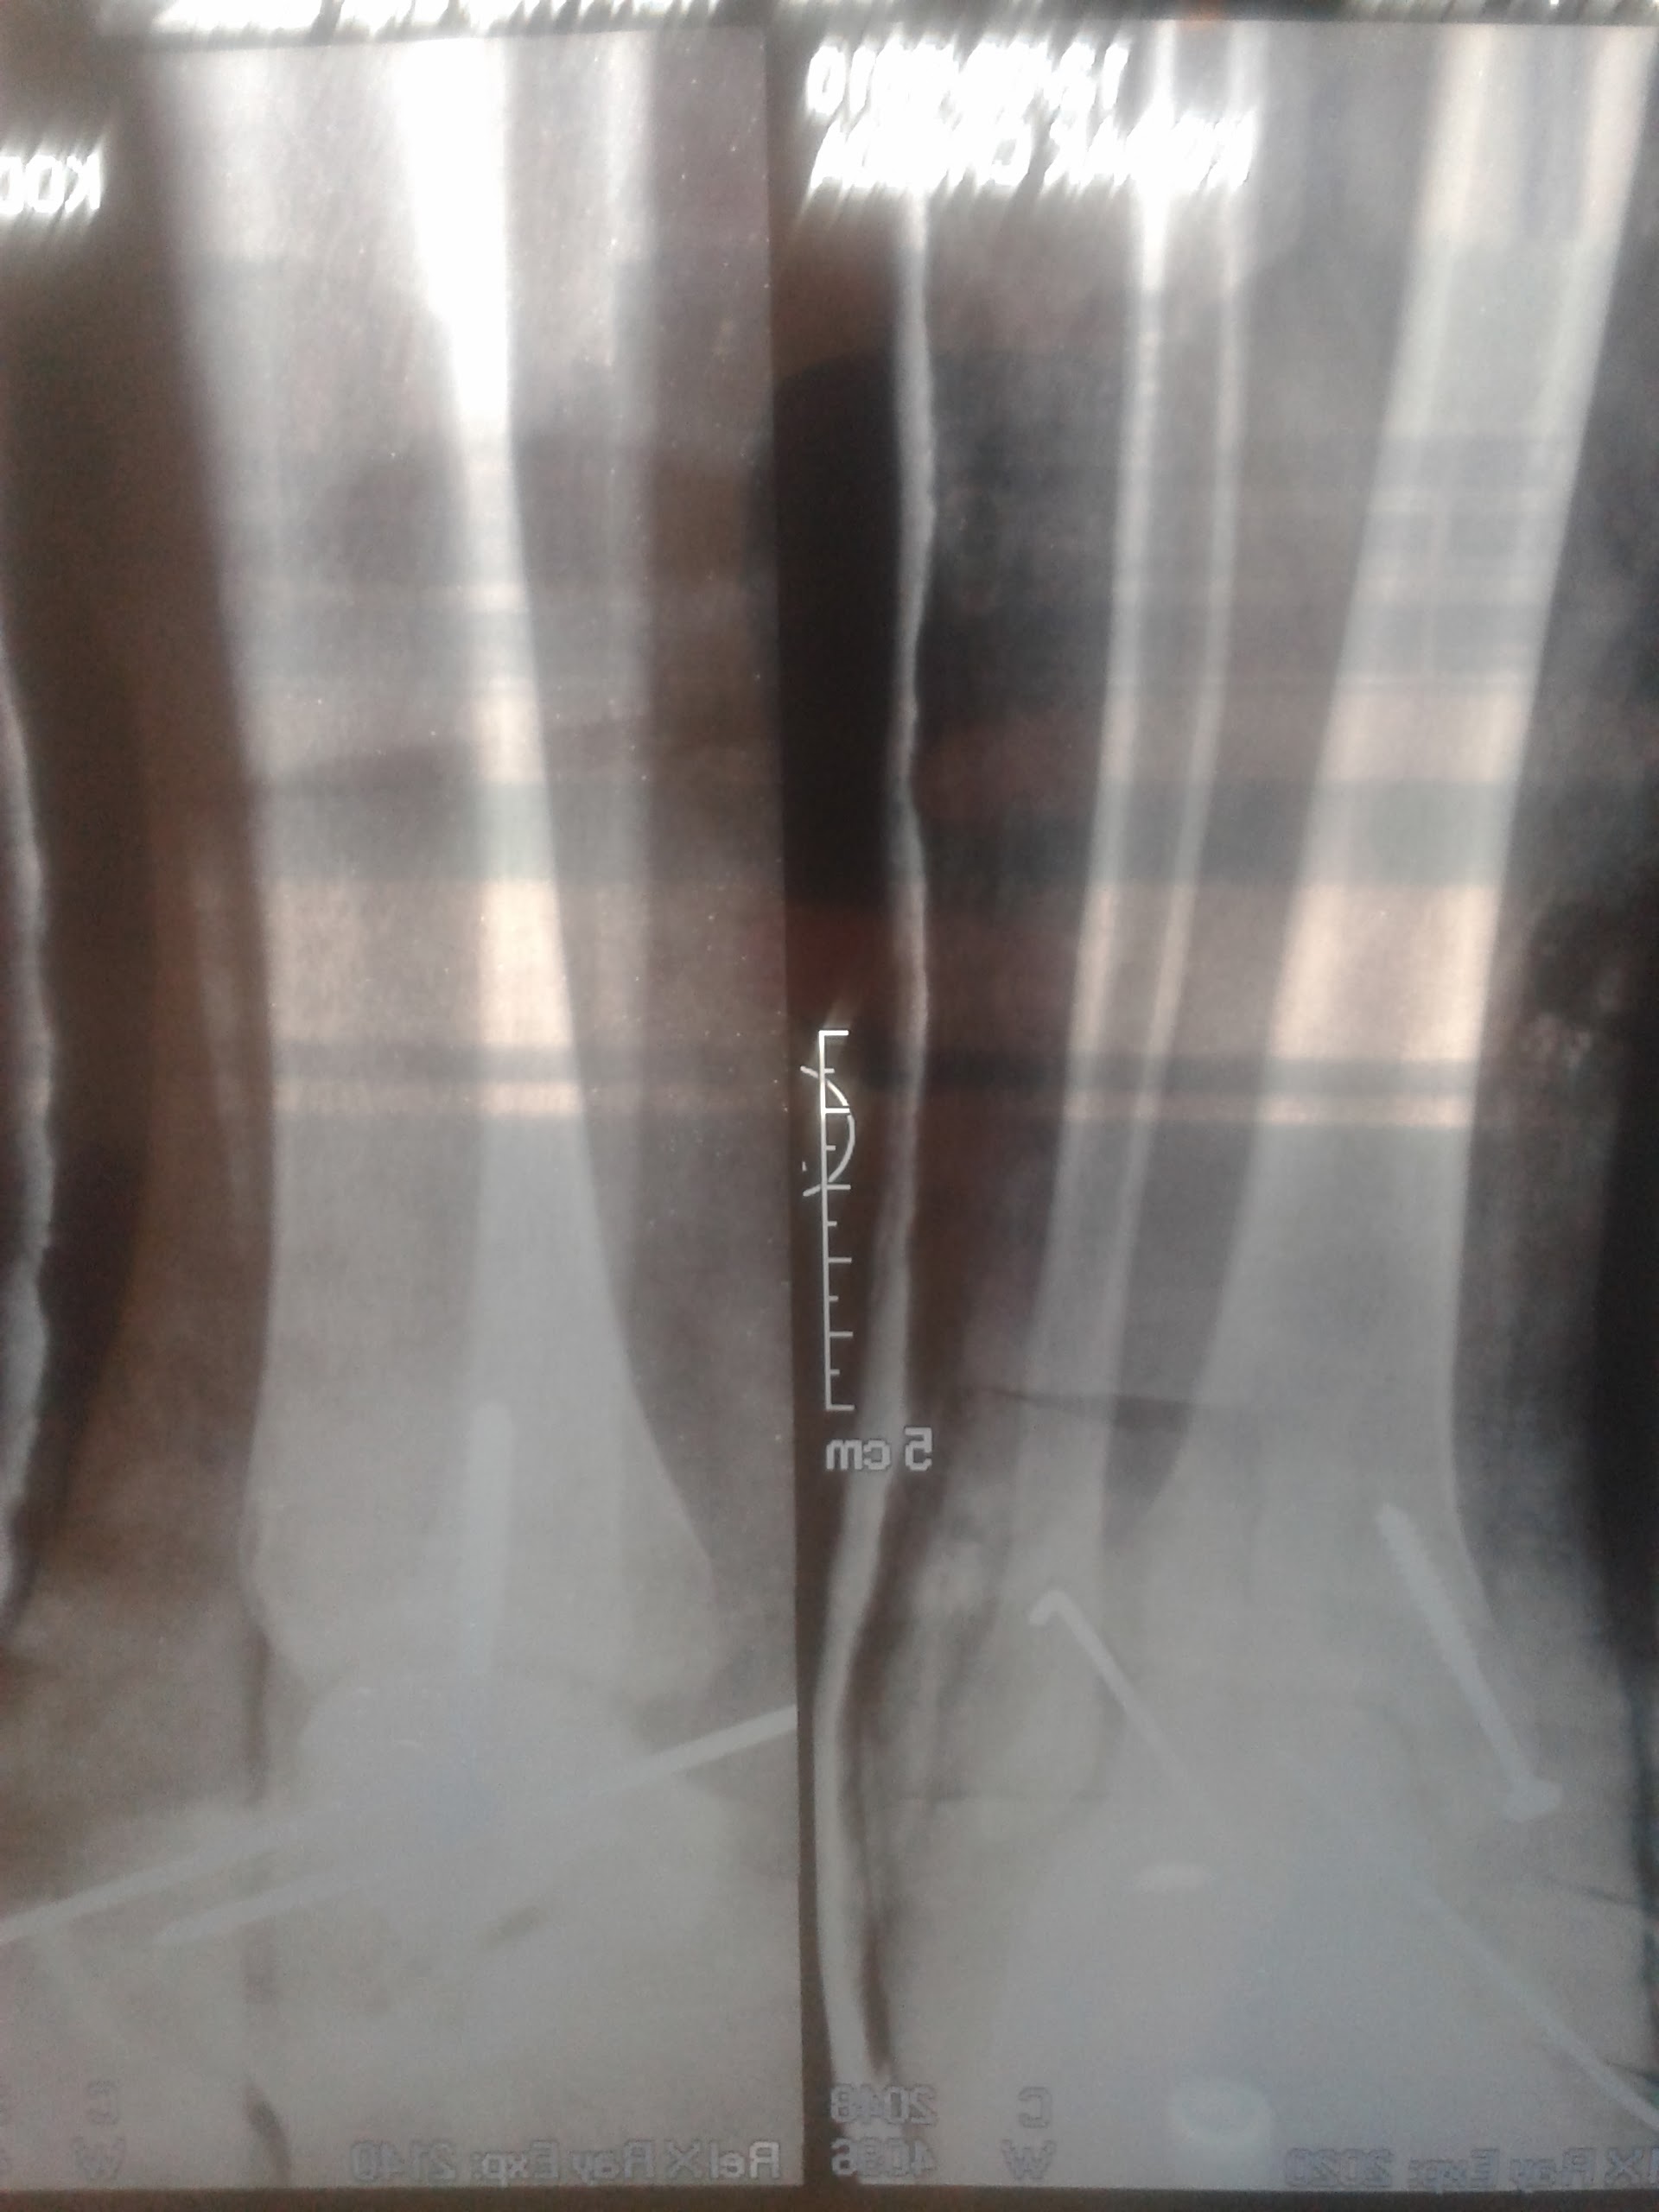

Astragalectomía. Evaluaciones funcional y radiográfica. [Talectomy. Functional and radiological evaluation]